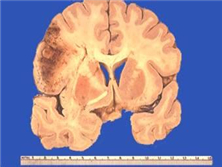

神經(jīng)元蠟樣脂褐質(zhì)沉積癥是一組兒童最常見的遺傳性進(jìn)行性神經(jīng)系統(tǒng)變性病。雖然多數(shù)患者在兒童期發(fā)病,偶爾也出現(xiàn)在成年人。其臨床特點(diǎn)包括進(jìn)行性癡呆、難治性癲癇發(fā)作和視力喪失。在病理上表現(xiàn)為具有黃色自發(fā)熒光特性的脂色素沉積在神經(jīng)細(xì)胞和其他細(xì)胞內(nèi),導(dǎo)致以大腦皮質(zhì)和視網(wǎng)膜為主的神經(jīng)細(xì)胞脫失。超微結(jié)構(gòu)檢查發(fā)現(xiàn)脂色素在不同的臨床亞型由顆... [詳情]